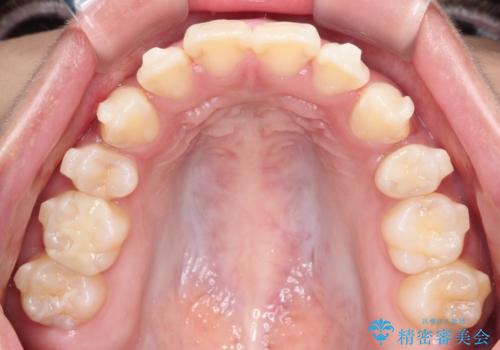

【インビザライン】シザーズバイト、抜歯矯正

- オープンバイトを主訴に来院された患者様です。

抜歯を行うことで、インビザラインを用いて前歯を下げることができ、同時にオープンバイトを改善することができました。

今回はインビザラインのみで治療を終了することができました。